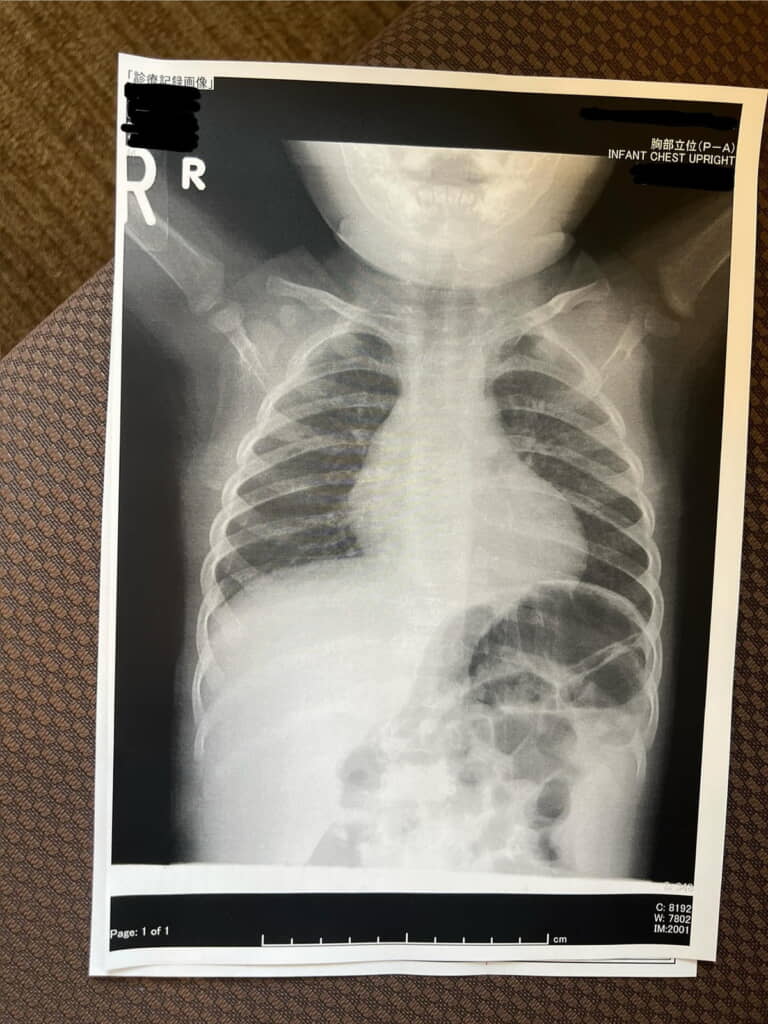

息子さんはぷっくぷくのフェイスラインがとても愛らしい男の子。ある日、諸事情のため病院でレントゲンを撮影することになりました。撮影後の写真の顔あたりを見たところ……そこには思いがけないものが写っていたのです!

それは、もっちりとしたお肉の影に隠れたしゅっと美しい骨格。予想以上に小さな骨格に驚くのみならず、骨を力強く守るようにして存在するぷくぷくフェイスラインにキュンキュンします。これだけたっぷりと包みこんでいたら、やわらかもちもちほっぺになるのも納得です。ママさんは「顔の外周に無駄な脂肪しかなくて」「撮影後見せてもらって可愛すぎてひっくり返った」とコメントしています。

投稿には「レントゲンの時点で可愛い…」「しゅっとしたフェイスラインがちゃんと中に隠れてますね」「愛が詰まってますね!」「てことは、お顔スッキリしたらめちゃ小顔ですね」「お口の所がおちょぼ口みたいに見えてさらにキュンがマシマシでした」「やばい、めちゃくちゃかわいい」といった声が寄せられています。